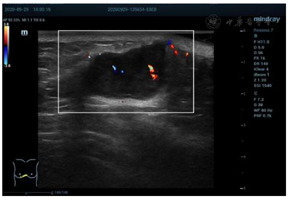

乳腺超声显示(图1):右侧乳腺5点半距乳头8~10 cm腺体边缘近胸骨旁扫见混合回声结节,大小约26 mm×15 mm,距体表6 mm,边界清晰,形态欠规则,内部回声欠均匀,后方回声略增强,CDFI:可见少许血流信号(图2)。弹性成像显示肿块硬度尚可(图3)诊断为BI-RADS 4a类,建议行乳腺超声造影。行超声造影后提示:增强早期肿块与周围乳腺组织相比,造影剂呈向心性、快进、高增强(图4),分布均匀,周边未见明显滋养血管,造影后范围30 mm×17 mm,大于二维超声;增强晚期造影剂缓慢消退,诊断为BI-RADS 4c类。